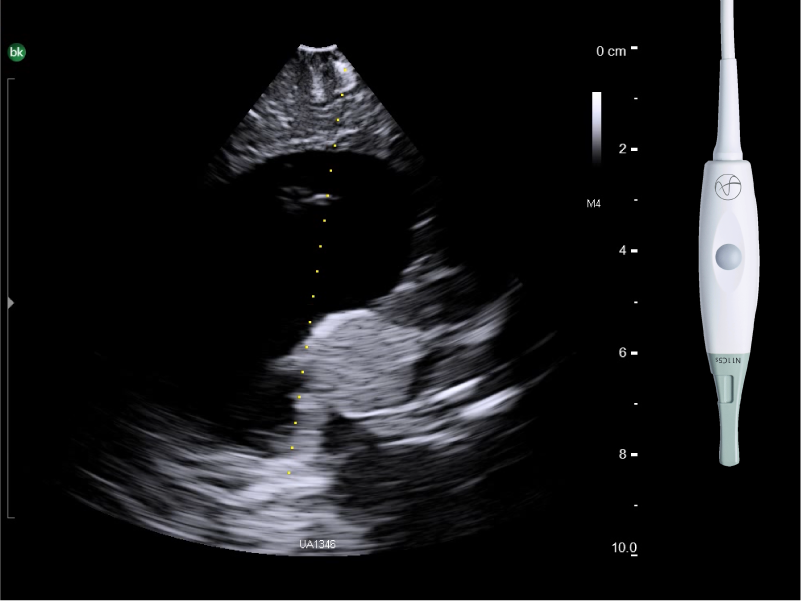

REAL-TIME VISUALIZATION HAS NEVER LOOKED THIS GOOD

- Enhanced Visualization: Improved algorithms for greater details around lesion borders, and automated high-resolution image settings.

- Monitor Progress: Compare live images with previous scans simultaneously using Dual Live Compare, Picture in Picture, or Stored Image Compare.